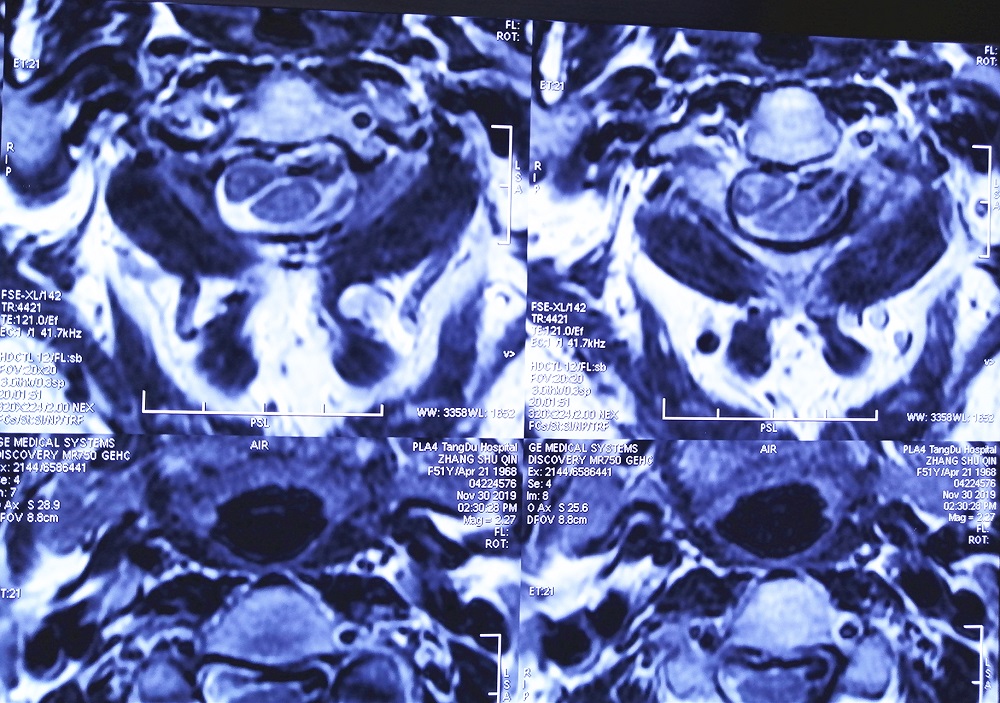

结果颈椎核磁共振检查发现,马女士颈2椎管内肿瘤(术后病理检查为脊膜瘤),颈5-6、6-7出现颈椎间盘突出,并且还有颈椎骨质增生。

术前影像学检查